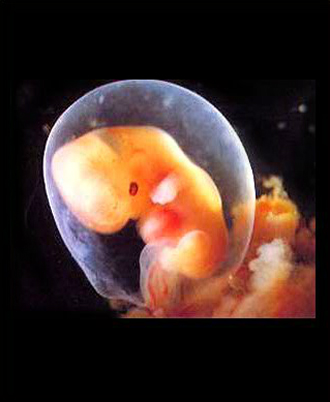

- 10주 이전

- 질 초음파 (1회/2주)

- 산모종합검사 (풍진, 간염, 매독, 에이즈, 빈혈, 혈액형, 갑상선, 소변검사)

- 10주 이후

- 초기 정밀 초음파

- 복부 초음파